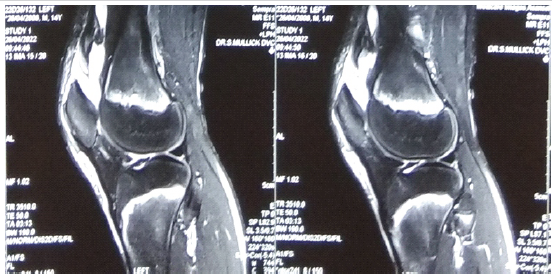

A 14-year-old male patient with a body weight of 30 kg came to our department with left knee pain after an alleged history of trauma while playing football 2 days back. On clinical examination, pain over the left knee was encountered, there was a palpable gap over the left patella, and the patient could not do active straight leg raising. After doing a proper investigation, it was seen in the MRI that the quadriceps of the left side are completely ruptured and got erased from the patellar surface (Fig. 1).

Figure 1: Pre-operative magnetic resonance imaging of the patient showing quadriceps tear.